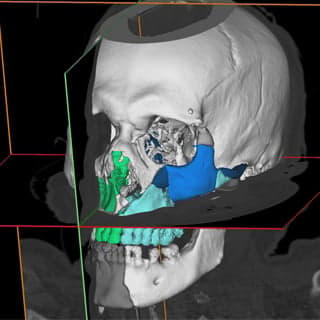

Combined Exoscopic and Endoscopic Technique for Craniofacial, VSP Craniomaxillofacial Solutions | 3D Systems

VSP Craniomaxillofacial Solutions | 3D Systemsクインテッセンス インプラント周囲円はEr:YAG Laserでこう治す!